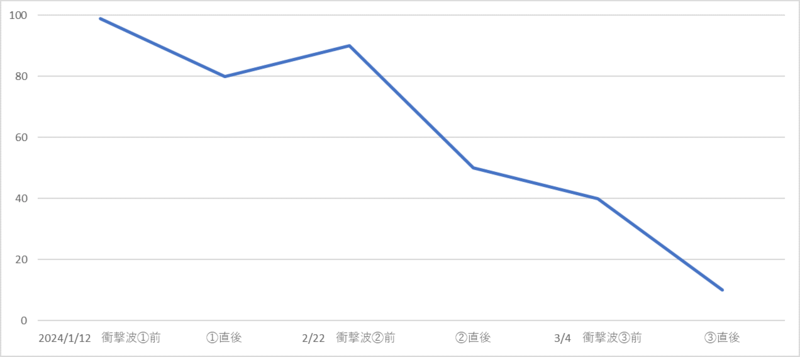

下に治療中の疼痛推移を示します。

体外衝撃波は3回施行し、漸減的に疼痛が軽減していきました。

制限なく趣味活動に復帰できたため通院終了となりました。

縦軸:痛みの強さ 最も痛い:100 痛くない:0

横軸:時間軸